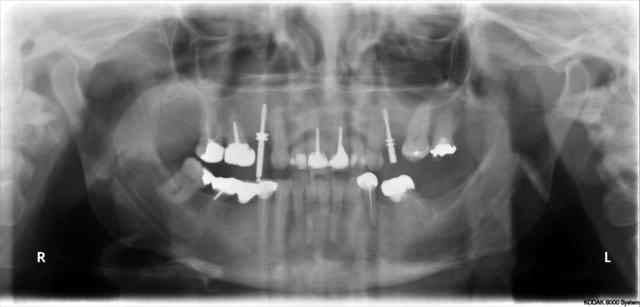

tiens...un ptit cas...

dans ce petit cas...j'ai commencé avec le kit MIS...et fini ma voie crestale avec le kit HBS...

ok, c'est un mini soulevé...mais bon , c'est un exemple...

juste une précision...premier foret 1.3mm sur 8mm...expansion pour mettre un implant de 4x10...

j'ai juste "léché" la préparation du site final avec le foret terminal du système...sur 8mm...avant d'insérer l'implant...stab primaire au top...blocage à 40 Ncm...

???? tu as un pano ou un scan je ne situe pas ça comme une cloison, mais je vois mal.

j'ai la pano au cab...pas de problème...çà peut aussi être un épaississement de la membrane dans ce cloisonnement...il a eu un bon rhume quelques semaines avant...